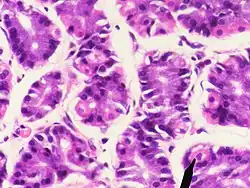

Humane Belegzellen (eosinophil, eine Zelle markiert), Hauptzellen (basophil)

Die Belegzellen (Exocrinocyti parietales, auch Parietalzellen) liegen zwischen den übrigen Zellen oder ihnen außen an. Sie sezernieren Protonen, die sich extrazellulär mit Chloridionen zu Salzsäure zusammenlagern, und den für die Cobalamin-Resorption (Vitamin B12) notwendigen intrinsischen Faktor. Die Zellen bilden intrazelluläre Sekretkanäle mit Mikrovilli. Diese Kanäle werden im aktiven Zustand der Zellen in die luminale (zum Magenraum gerichtete) Plasmamembran eingebaut und vergrößern so die Kontakt- und Abgabefläche. Hier befinden sich Protonen-Kalium-Pumpen, die Protonen im Austausch gegen Kaliumionen aus der Zelle transportieren. Belegzellen sind relativ groß und eosinophil (mit Eosin anfärbbar und daher rötlich).[1]

Die Hauptzellen (Exocrinocyti principales) im Hauptteil der Magendrüsen sind hochprismatisch mit einem basal liegenden Zellkern. Sie bilden Pepsinogene, die Vorstufen verschiedener Enzyme, die zusammengefasst als Pepsine bezeichnet werden (bei Wiederkäuern das Lab). Sie werden in sogenannten Zymogengranula in den Zellen zwischengespeichert. Hauptzellen sind durch den großen Anteil an rauem Endoplasmatischem Retikulum (rER) basophil (mit basophilen Farbstoffen anfärbbar, daher bläulich).[1]